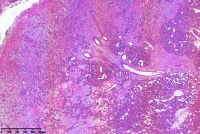

肉芽肿型血管瘤?

女

60岁

右手小指包块3年

右手小指包块

同意楼主意见,毛细血管瘤(肉芽肿型)。

肉芽型毛细血管瘤。